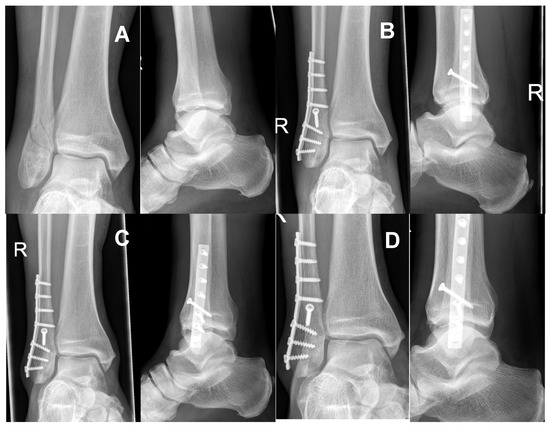

2.2. Surgical Technique and Postoperative Therapy

3.3. Radiological Follow Up